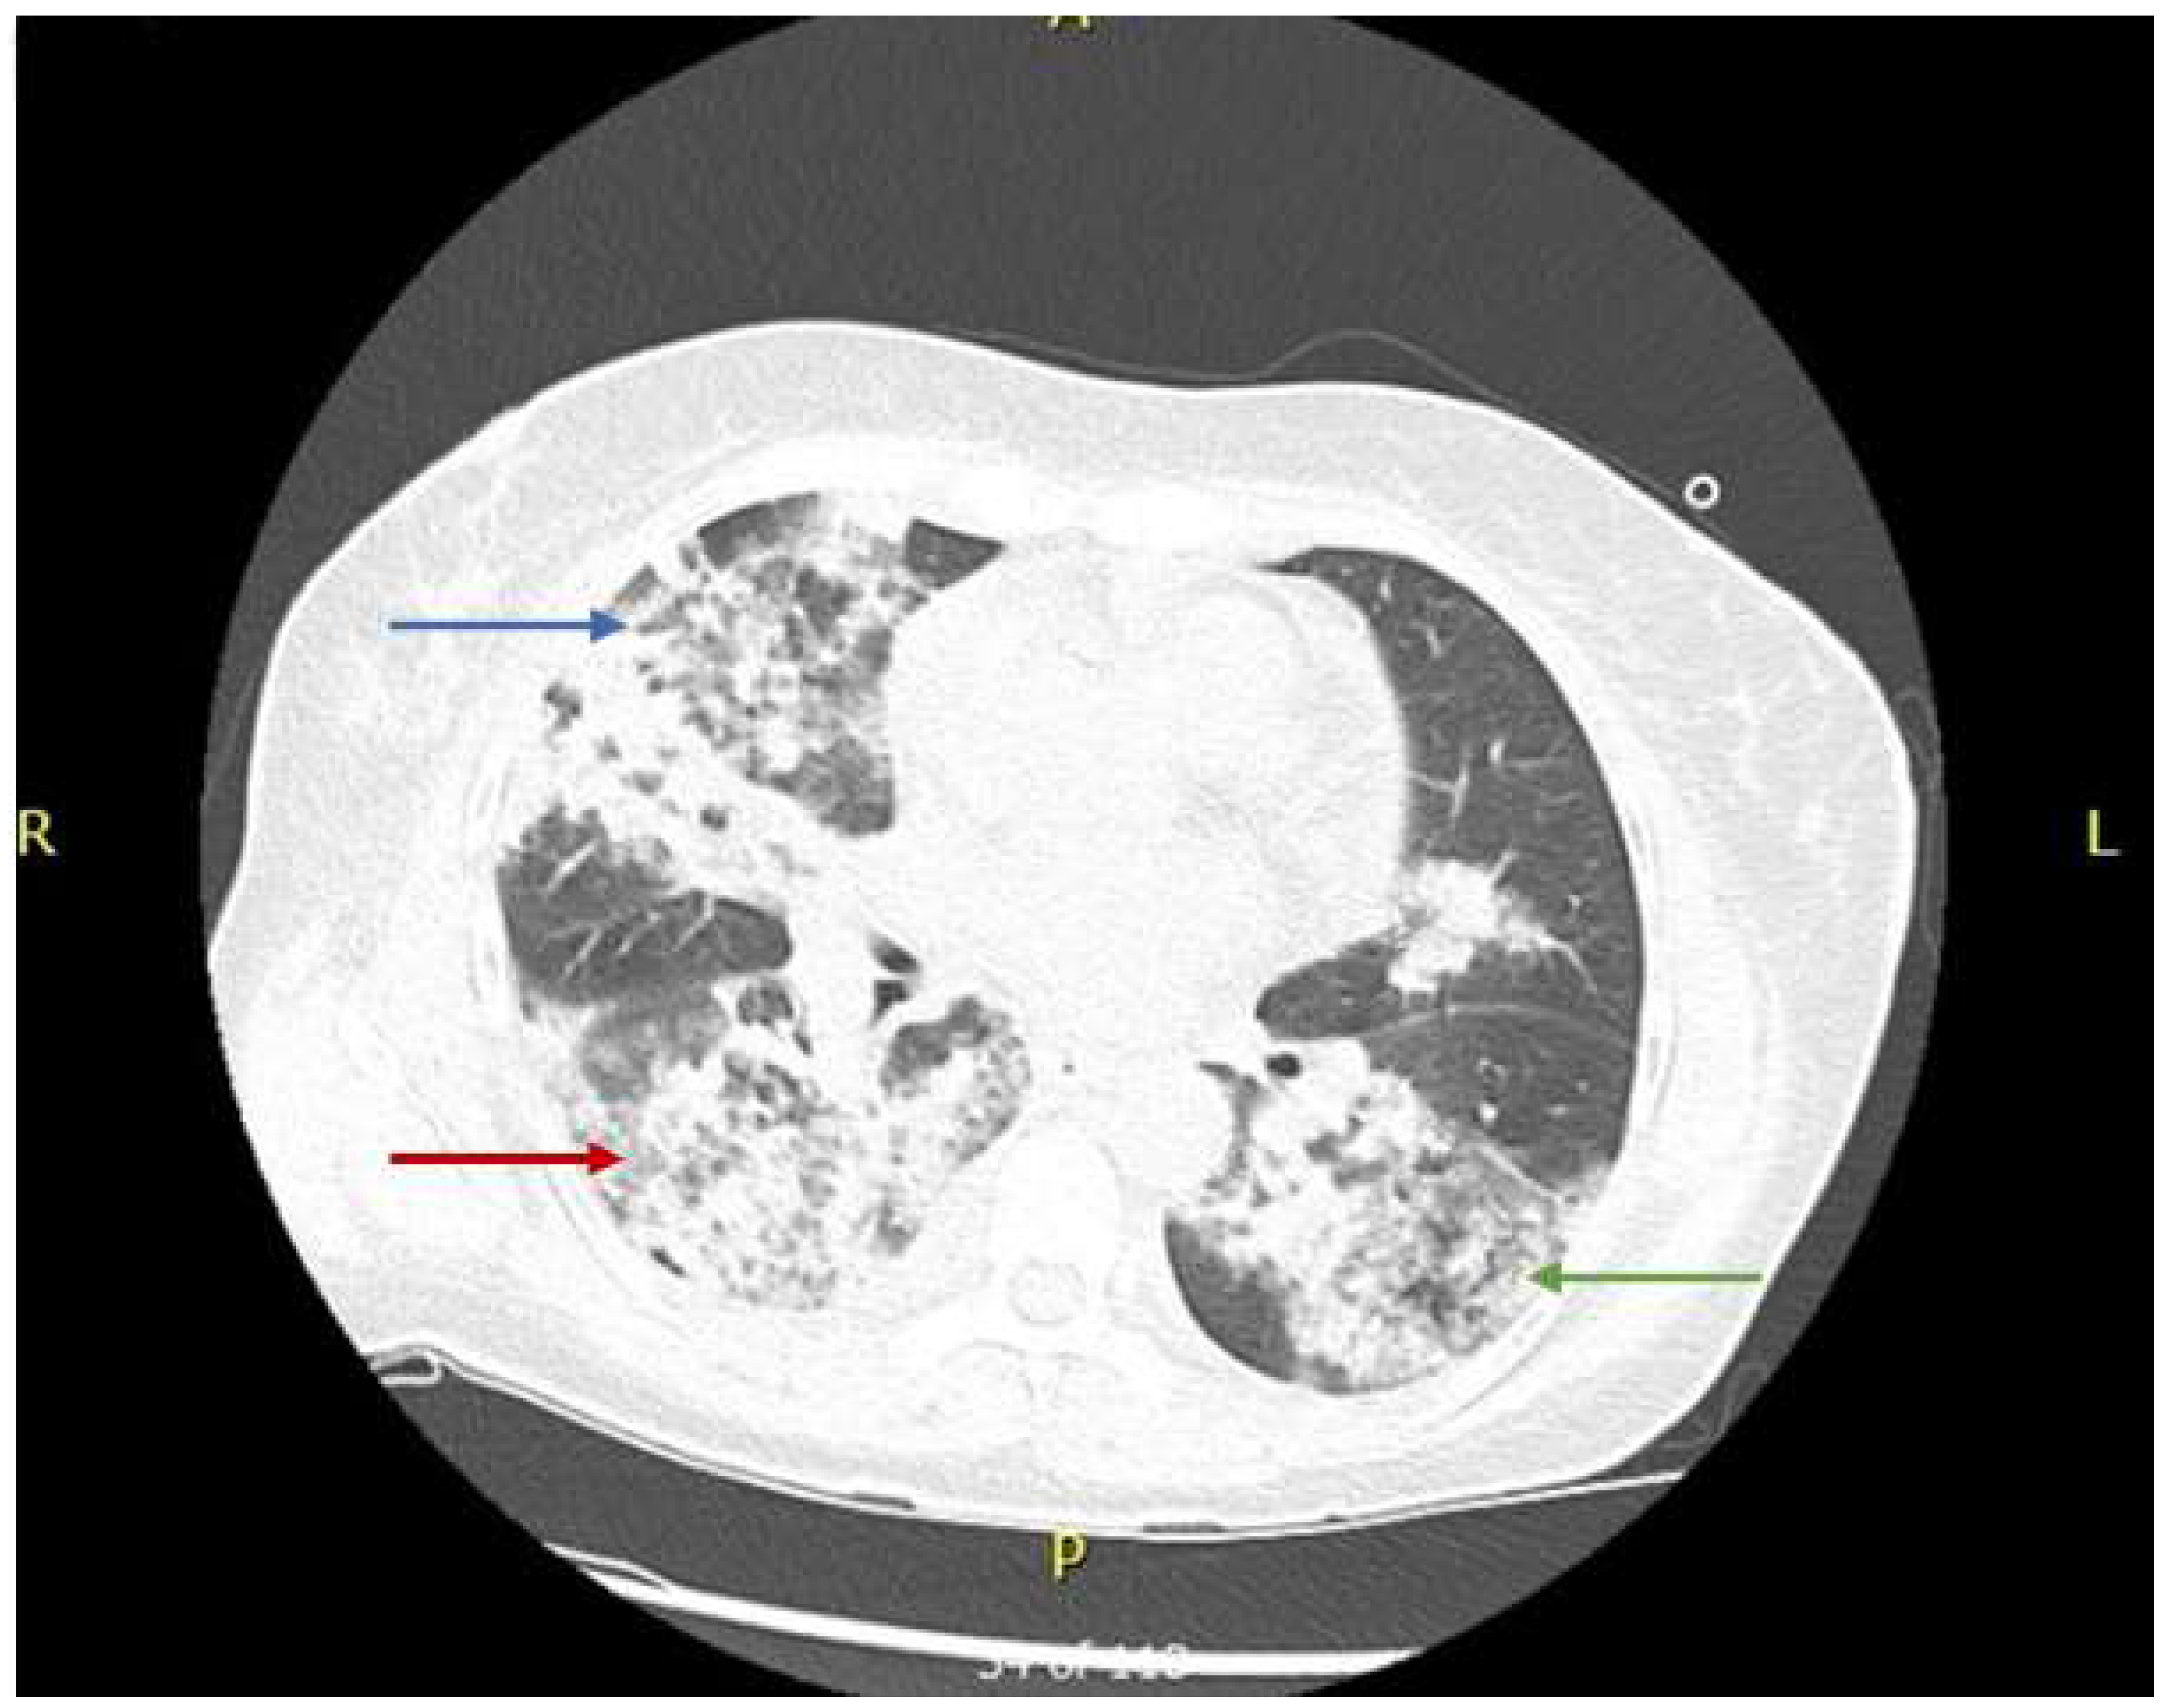

- Abnormal chest radiography scans showing nodules, fixed infiltrates, or cavities.